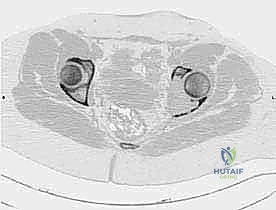

- التصوير المقطعي المحوسب (CT Scan): يقدم صوراً ثلاثية الأبعاد تُظهر بدقة متناهية مدى تدمير القشرة العظمية، وهو الفحص الأهم للتخطيط الجراحي وتحديد خطر حدوث الكسور المرضية.

- التصوير بالرنين المغناطيسي (MRI): الفحص الأفضل لتقييم امتداد الورم خارج العظم إلى الأنسجة الرخوة (العضلات، الأوعية الدموية، الأعصاب) وتقييم مدى إصابة نخاع العظم.